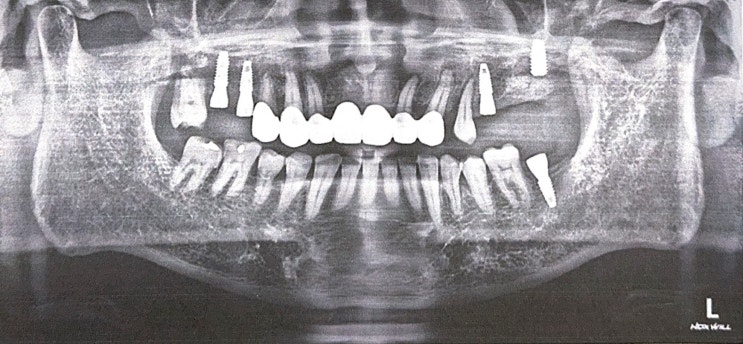

?앞니 브릿지 치료 최종 완료, 내가 의사에게 물어본 것은?

지난 보철물 임시 부착 후 2주가 지나고 드디어 ?앞니 브릿지 치료가 최종 완료되었습니다. 보철물 임시...